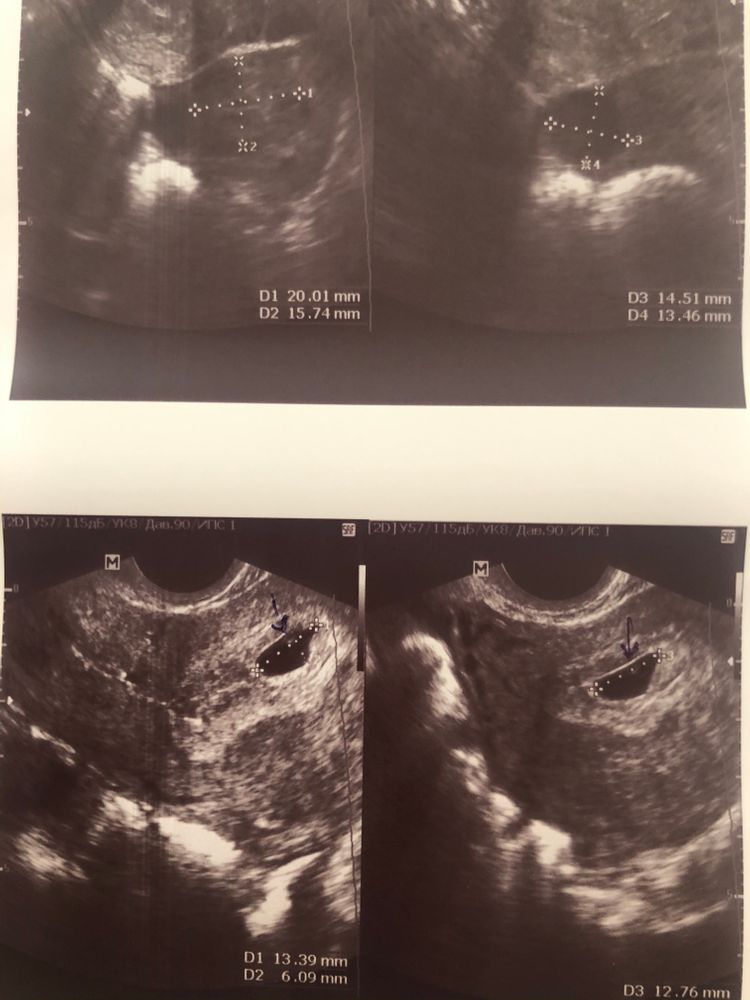

Сделала сегодня узи , у меня 6 дней задержки, если по циклу считать то срок 5,5 недель, но у меня цикл 34 дня и овуляция на 19-20 день обычно, так что я не знаю. То есть это примерно 3 недели с овуляции.

По узи - эмбриона в плодном Яйце не видно как и сердцебиения соотвественно. Свд размер 10,7 мм.

Узист говорит что не может сказать зб это или нет, но ей не понравились контуры плодного Яйца - типа неровные ...